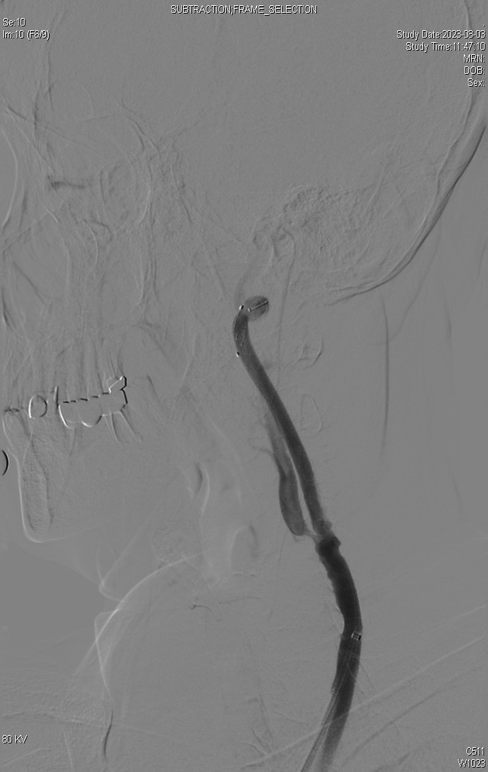

CASE 1:79岁男性,双侧颈动脉重度钙化狭窄,采用IVL预处理后置入支架,术后造影显示管腔通畅。

双侧颈动脉重度

钙化狭窄

IVL后管腔

获得良好

术后造影

显示管腔通畅